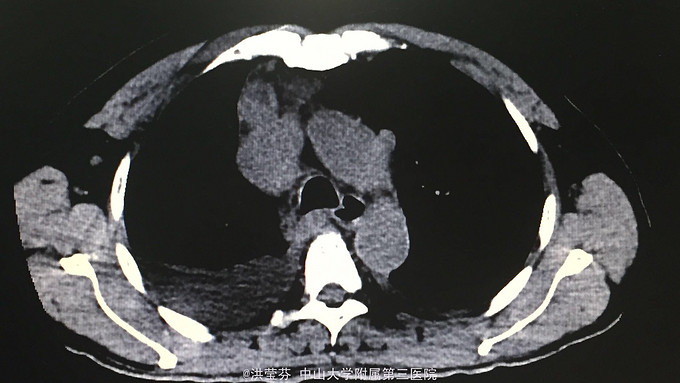

查体:KPS 60分,BSA 1.83m2,T 38.5℃,全身浅表淋巴结未触及明显肿大,胸壁可见浅表静脉曲张,呼吸急促,左下肺、右中下肺呼吸音明显减弱,其余肺野呼吸音促,可闻及少许实性啰音,心率110bpm,律齐,腹软,全腹无压痛、反跳痛,未扪及明显包块,肝脾肋下未触及,移动性浊音(——),肠鸣音正常,4次/分,双下肢无凹陷性水肿。 辅助检查:血常规无特殊,生化转氨酶稍升高,低钠低氯,CRP 227.9mg/L,凝血四项:Fib 8.14g/L。复查胸部CT提示:1.胸腺癌并纵膈淋巴结及双肺多发转移瘤,右心房、上腔静脉受侵并癌栓形成,病变较前进展。2.双肺炎症,以右肺为著。3.双侧胸腔及心包积液。上腹部CT提示:1.下腔静脉早显并肝表面多发侧支形成,考虑右心流出道阻塞所致;腹壁静脉曲张。头颅MR提示右侧颞叶强化灶,结合病史,考虑转移瘤,伴瘤灶少量出血可能,瘤周脑水肿。

入院诊断:1.A型胸腺瘤并纵膈淋巴结、双肺、脑转移,2.上腔静脉血栓形成(癌栓)。入院后予利尿、甲强龙减轻水肿和压迫治疗,“亚胺培南”抗感染治疗后咳嗽、气促症状较前明显缓解,提问逐渐恢复正常,后予CIK免疫细胞回输治疗。